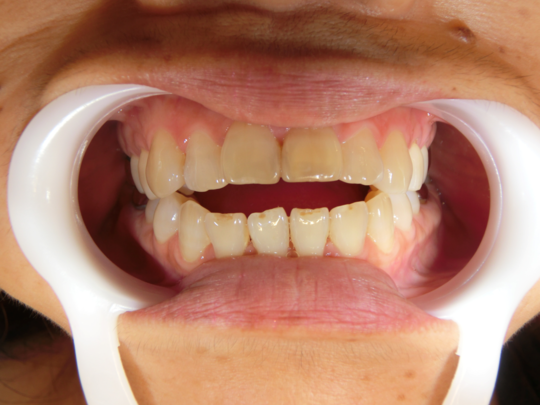

治療前

治療説明 歯科矯正でも目立ちにくい矯正方法であるマウスピース矯正で治療しました

治療期間 1年1か月

治療費用498000 円